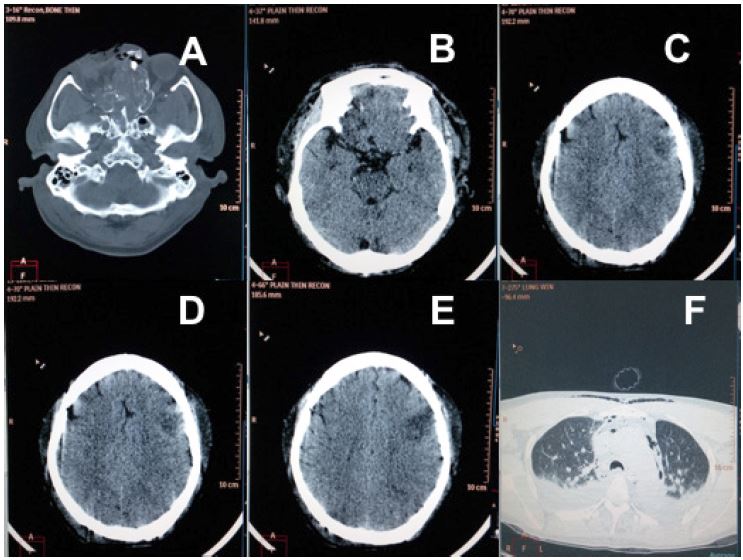

Fig 2 (Case 2: Gunshot wound Neck): Magnetic resonance revealing (A) Comminuted posterior fracture of C4 and C5, cord compression and edema extending from C3 to C6 vertebrae (B-D) Watershed infarct of right middle and posterior cerebral arteries, and occlusion of internal carotid artery.

A 48-year-old combatant sustained gunshot injury at the angle of right mandible involving the face and neck in a CI/CT operation. He was resuscitated from hypovolemic shock, cardiac arrest and initiated on mechanical ventilation. Evaluation of the head and neck through NCCT and magnetic resonance imaging revealed cerebral oedema, watershed infarct of right middle and posterior cerebral arteries, occlusion of the internal carotid artery, cord compression and cord oedema, comminuted displaced fracture of right mandible and comminuted fracture of C4 and C5 vertebrae.(Figure 2) He was air evacuated on ventilator support under sedation to a tertiary care facility the same day where his GCS was E1VETM1 (sedated) with bilaterally sluggish pupils and quadriplegia.